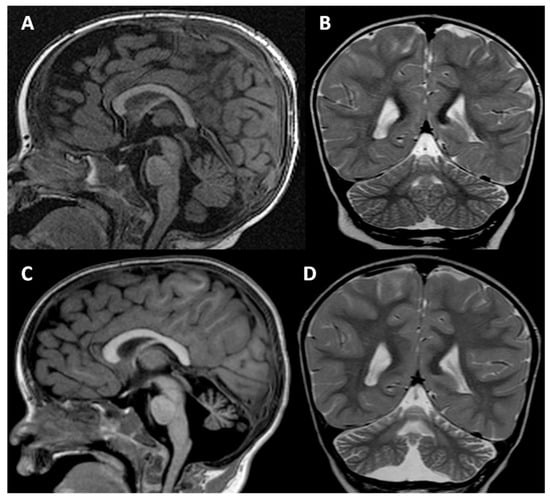

2. Clinical Report